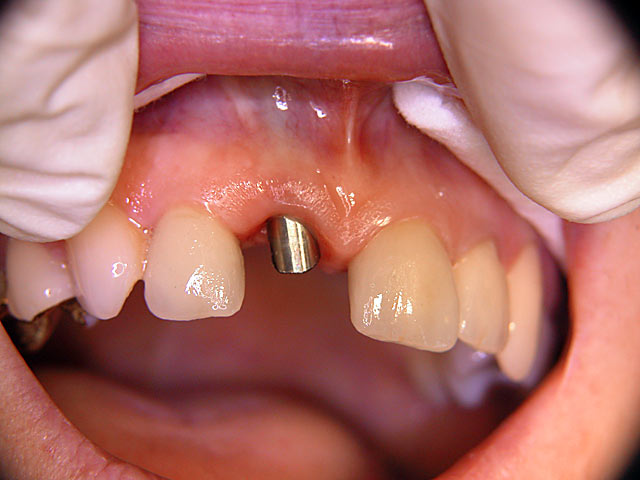

Frontzahn-Implantation: